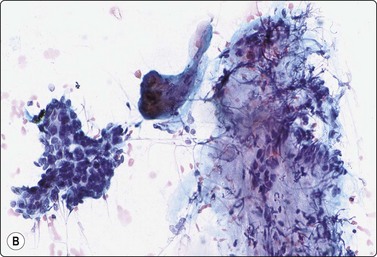

Paraganglioma (carotid body and glomus jugulare tumors) (Figs 4.11-4.13)5,50-52

image

Fig. 4.11 Paraganglioma

CT scan showing large solid mass in left oropharynx; paraganglioma diagnosed by FNB.

image image

Fig. 4.12 Paraganglioma

Loosely clustered cells; suggestion of follicular arrangement resembling thyroid epithelium; anisokaryosis and ‘speckled’ chromatin (Pap) typical of neuroendocrine tumors. Very fine eosinophilic cytoplasmic granules visible under the microscope but not in photograph; (A, MGG, HP; B, Pap, HP).

Fig. 4.13 Paraganglioma (atypical)

(A) Smear showing prominent anisokaryosis but a uniformly bland chromatin pattern (MGG, HP); (B) Tissue section of the same case (H&E, IP).

Criteria for diagnosis

Neoplastic cells single and loosely clustered, often forming curved rows or a vaguely follicular pattern; bloody background,

Abundant pale cytoplasm with indistinct cell borders,

A fine red cytoplasmic granulation (MGG) may be seen in some cells,

Nuclei rounded to spindle with granular or speckled, evenly distributed chromatin,

Variable anisokaryosis; scattered single cells with considerably enlarged nuclei, some bi-nucleate, in a background of generally uniform nuclei is characteristic,

Positive staining with neuroendocrine markers.

Problems and differential diagnosis

The cytological pattern is suggestive of an endocrine neoplasm and, given the anatomical site, the main differential diagnosis is a thyroid tumor. A follicular arrangement of the tumor cells may suggest a follicular carcinoma, but the fine red cytoplasmic granulation, the characteristic anisokaryosis and the presence of spindle cells closely resemble medullary carcinoma, and this is the main differential diagnosis (Fig. 4.12). Immune markers are helpful. Cells of paraganglioma stain positively for neuroendocrine markers. Staining for calcitonin is negative in most cases, but can occasionally be positive. Cytokeratin, thyroglobulin and TTF1 are negative. Intranuclear cytoplasmic inclusions as in papillary and some other carcinomas of the thyroid can be found in some paragangliomas.50 Knowledge of the exact anatomical site is obviously important. However, paraganglioma can occur in atypical locations including, although rarely, the thyroid. For example, one of our cases diagnosed by FNB had a tumor in the tonsillar region, clinically thought to be a deep parotid tumor (Fig. 4.11); another had a supraclavicular mass diagnosed clinically as lymphadenopathy. Both were histologically confirmed as paragangliomas.

Paraganglioma with a spindle cell pattern can mimic other spindle cell tumors in the neck such as spindle cell medullary carcinoma of thyroid and soft tissue tumors. Nuclear pleomorphism can sometimes be prominent enough to suggest malignancy (Fig. 4.13).5 As in other endocrine tumors, pleomorphism is not a reliable indicator of malignancy, mitotic rate and evidence of necrosis are better related to clinical behavior, and metastasis is the only definitive proof.

Paragangliomas are extremely vascular lesions and the aspirate often appears to be pure blood. If this is the case, smears may be non-diagnostic but diagnostic tissue fragments can sometimes be found in a cell block.